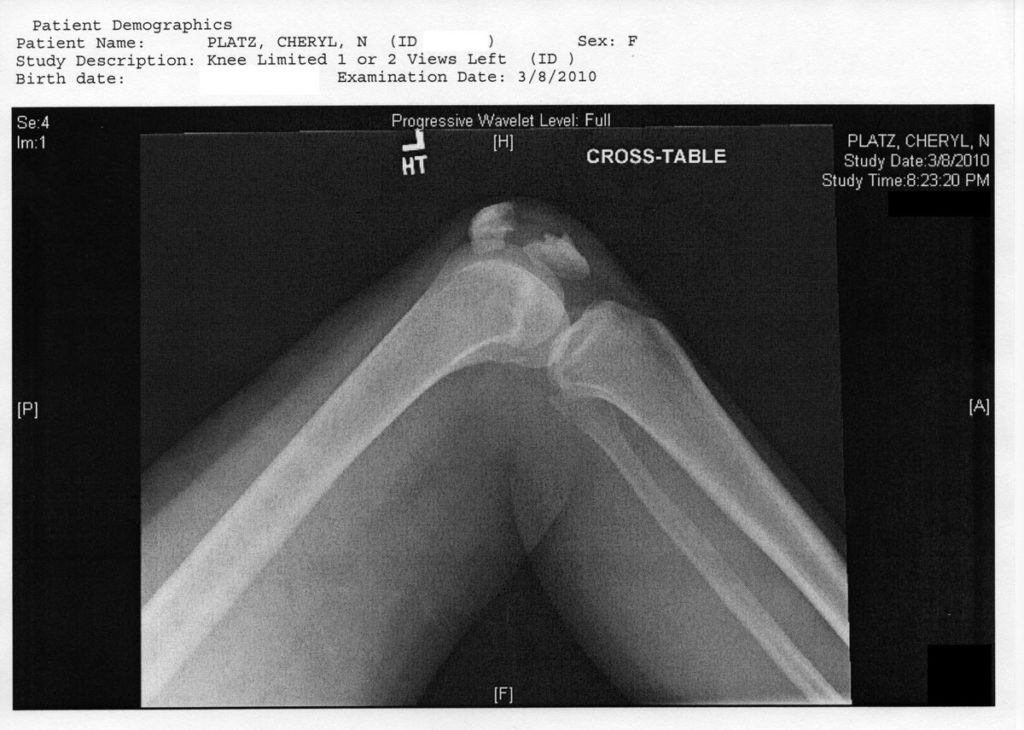

In March of 2010, I shattered my kneecap into five pieces. (If you want to know how I did it, I’ll just say that I told Leonard Nimoy that I broke it fighting crime on the moon, and he laughed, so now that’s my story.)

The injury was catastrophic and instantaneous. One moment I was walking, the next minute I was in unimaginable pain on the ground, screaming like a banshee. My brain literally reasoned that all of the planets in the universe must have converged on my kneecap at once to cause such a sensation. I don’t recommend it. Also, I was completely unable to move my leg, it was frozen in place. Which led to this before and after: